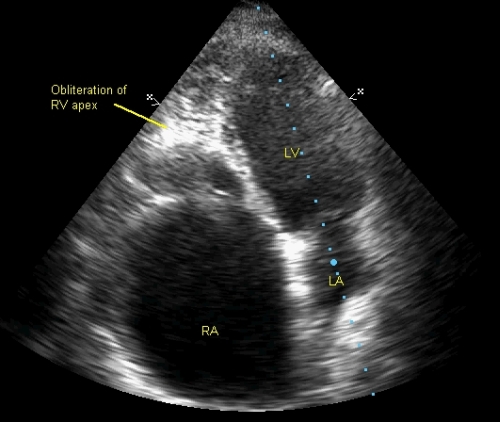

Right ventricular endomyocardial fibrosis – echocardiographic profile with video – All About Cardiovascular System and Disorders